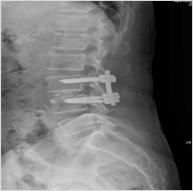

척추고정술

증상이 심한 척추분리증이나 척추전방전위증 혹은 척추관협착증이 심하여 수술시 척추관절을 많이 제거해야 하는 경우에 디스크 공간에 인공뼈를 삽입하여 낮아진 디스크 높이를 복원시켜주고 척추체가 잘 융합하여 움직이지 않게 하기 위하여 나사못을 이용하여 고정하는 수술이다.

적응증

• 척추분리증으로 만성 요통이 심한 환자

• 척추전방전위증이 심하여 신경증상이 있는 환자

• 여러 원인으로 척추불안정이 있어 이로 인한 요통이 심할 경우

• 심하게 재발된 척추 디스크

• 장기화된 디스크변성으로 인한 요통이 일반적인 치료로 호전되지 않을 경우

척추고정술 - 사진